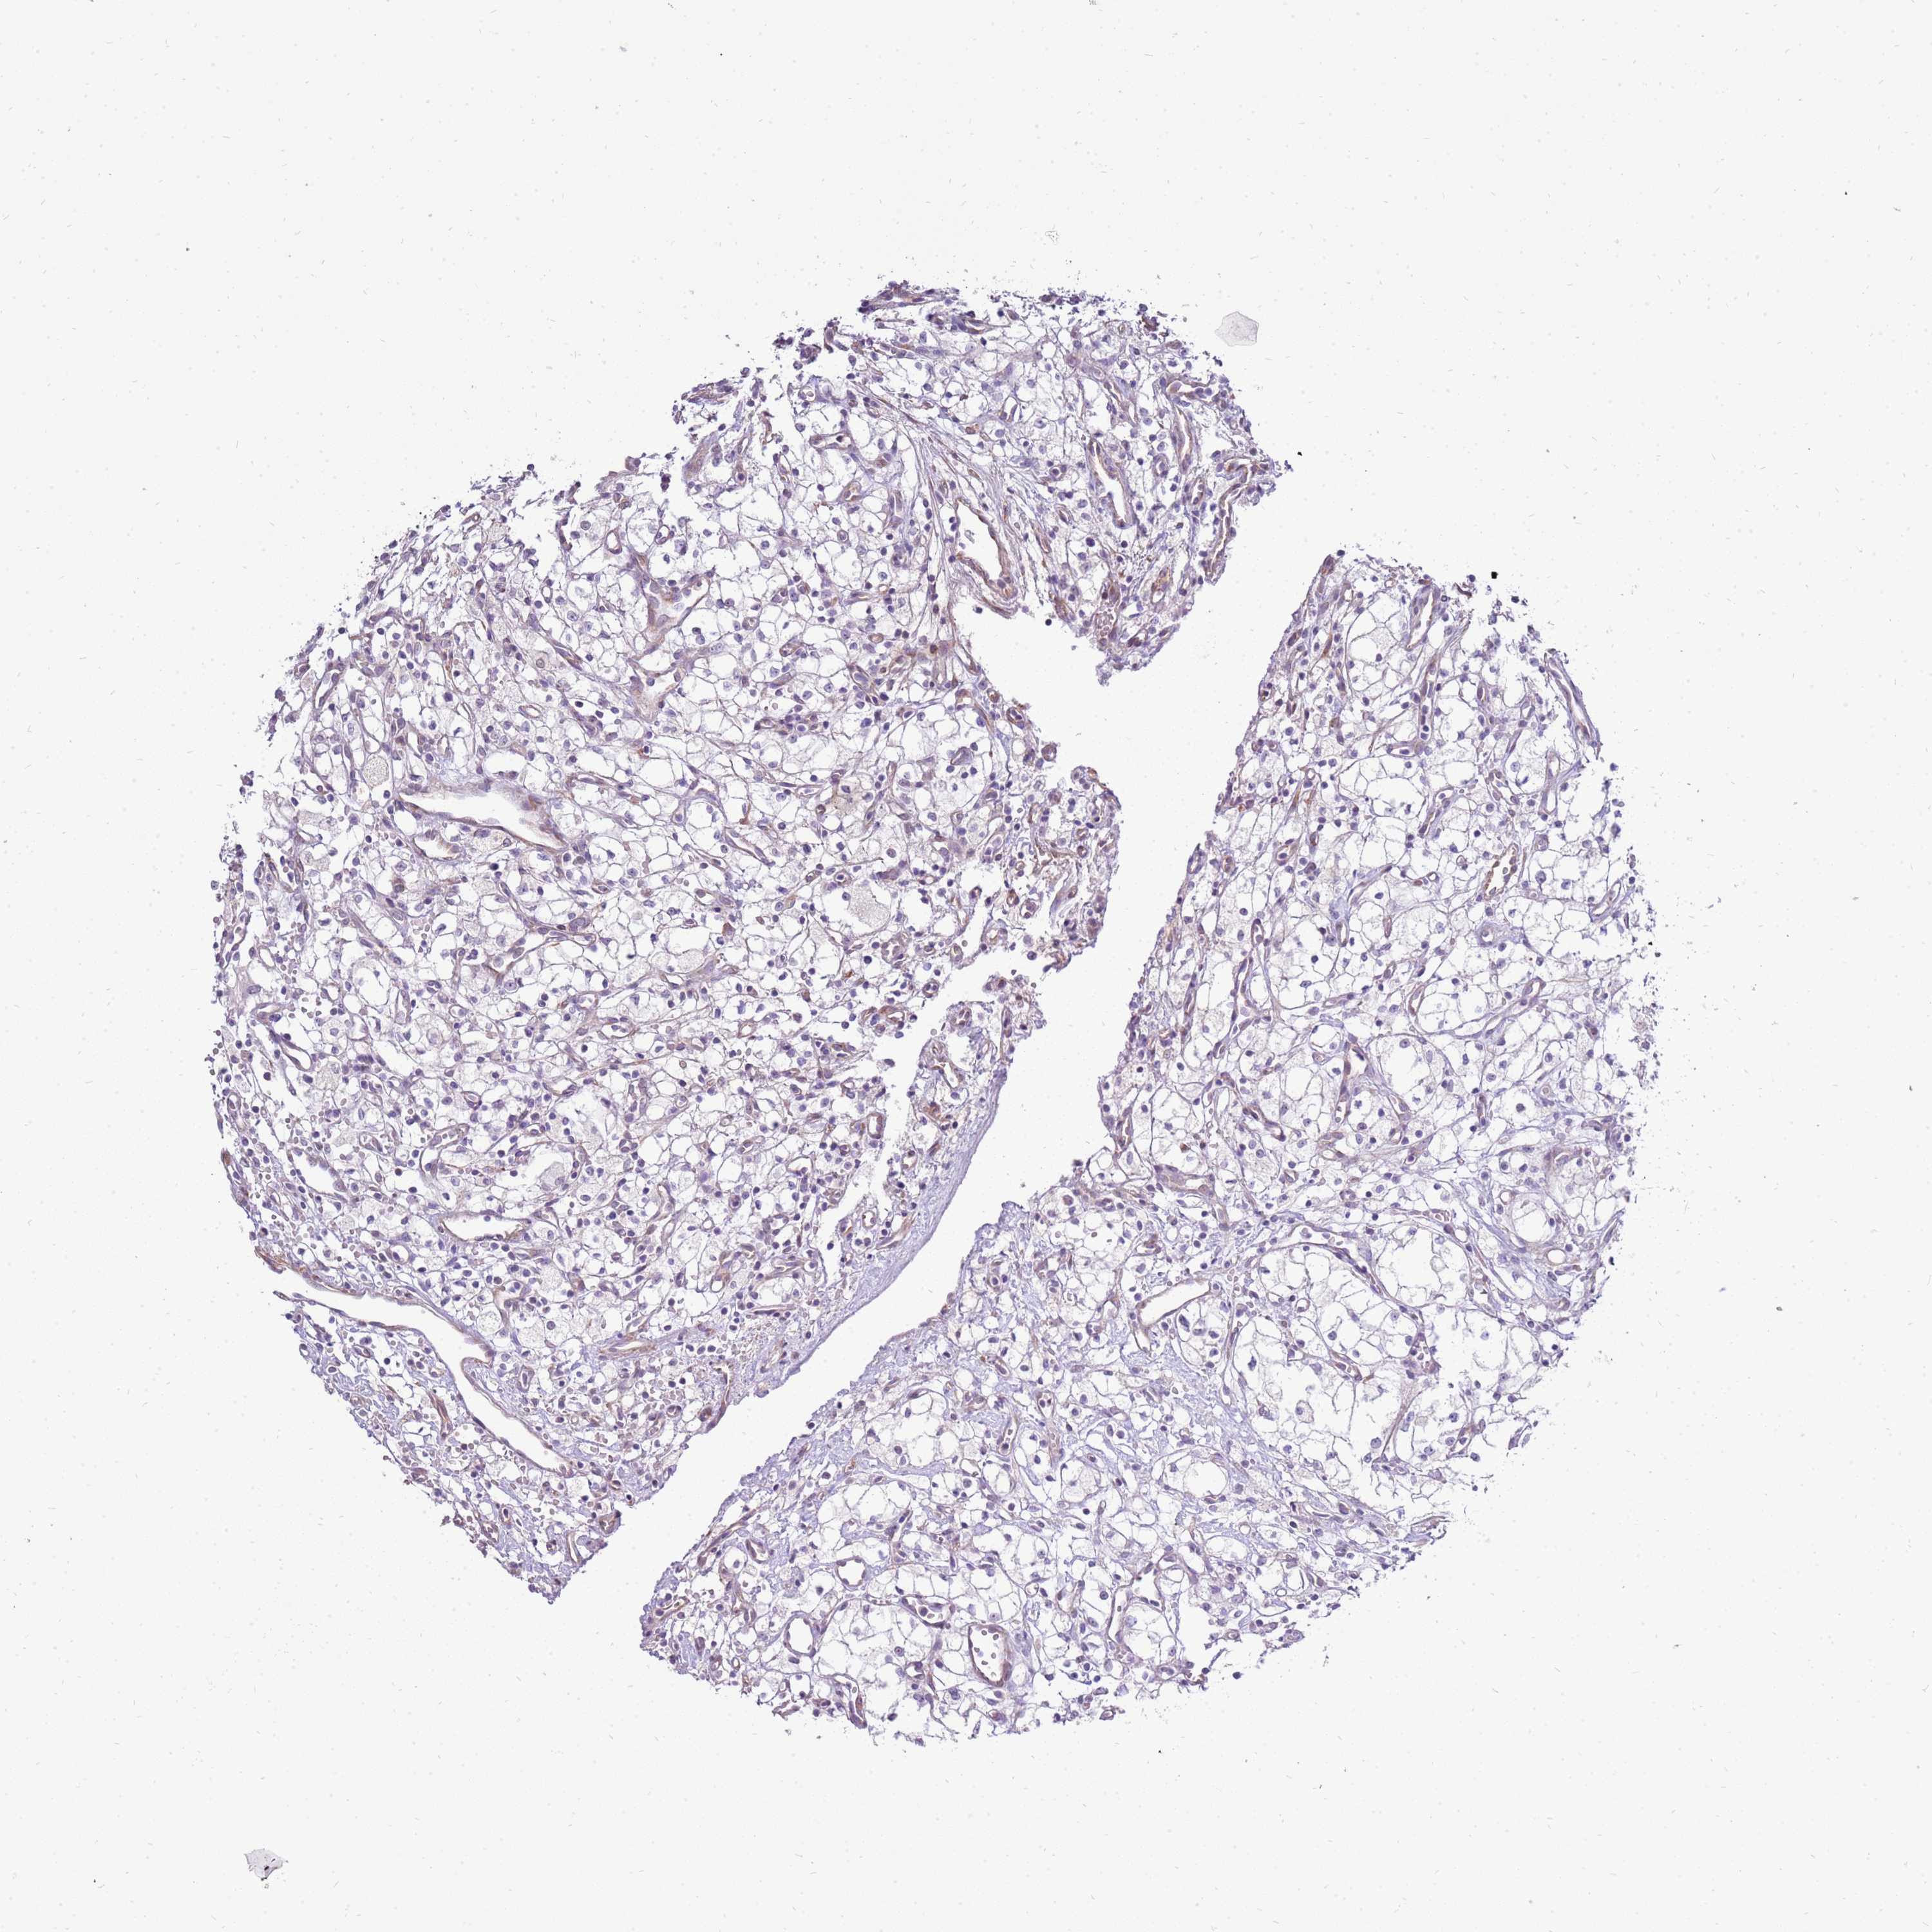

KIDNEY RENAL CLEAR CELL CARCINOMA (VALIDATION) - Interactive survival scatter ploti

The Survival Scatter plot shows the clinical status (i.e. dead or alive) for all individuals in the patient cohort, based on the same data that underlies the corresponding Kaplan-Meier plots. Patients that are alive at last time for follow-up are shown in blue and patients who have died during the study are shown in red.

The x-axis shows the expression levels (FPKM) of the investigated gene in the tumor tissue at the time of diagnosis. The y-axis shows the follow-up time after diagnosis (years). Both axes are complimented with kernel density curves demonstrating the data density over the axes. The top density plot shows the expression levels (FPKM) distribution among dead (red) and alive patients (blue). The right density plot shows the data density of the survived years of dead patients with high and low expression levels respectively, stratified using the cutoff indicated by the vertical dashed line through the Survival Scatter plot. This cutoff is automatically defined based on the FPKM cutoff that minimizes the p-score. The cutoff can be changed by dragging the vertical line or by entering a cutoff value in the square labeled "Current cut-off".

Under the Survival Scatter plot the p-score landscape (black curve; left axis) is shown together with dead median separation (red curve; right axis). Dead median separation is the difference in median mRNA expression between patients who have died with high and low expression, respectively. It is calculated as follows: median FPKM expression of dead patients with high expression - median FPKM expression of dead patients with low expression. This is intended to aid the user in visually exploring custom cutoffs and the associated p-scores and dead median separation.

Individual patient data is displayed and can be filtered by clicking on one or more of the category buttons on the top of the page. Categories describing expression level and patient information include: high, low, alive, dead, female, male and tumor stages. The scale of the x-axis can be toggled between linear and log-scale by clicking on the "x log" button. Mouse-over function shows TCGA ID, patient information and mRNA expression (FPKM) for each patient.

& Survival analysisi

Kaplan-Meier plots summarize results from analysis of correlation between mRNA expression level and patient survival. Patients were divided based on level of expression into one of the two groups "low" (under cut off) or "high" (over cut off). X-axis shows time for survival (years) and y-axis shows the probability of survival, where 1.0 corresponds to 100 percent.

UGGT2 is not prognostic in Kidney Renal Clear Cell Carcinoma (validation)

: 10.71

Average pTPM 11.1

Number of samples 100